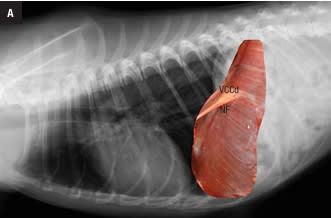

Este atlas de consulta rápida ayudará al clí­nico a obtener la máxima información de sus estudios radiográficos del tórax. Presenta gran cantidad de imágenes que guiarán al veterinario en su interpretación radiográfica, desde la misma técnica, la posición más idónea según la patologí­a que se sospeche o el estado clí­nico del paciente, o variaciones fisiológicas, hasta el órgano o estructuras torácicas a evaluar. Presenta montajes anatómico-radiográficos para ayudar a visualizar las estructuras que se están valorando en la radiografí­a. Aporta imágenes de las proyecciones radiográficas torácicas normales de más de 30 razas caninas para su comparación directa lo que hacen de este libro una guí­a de referencia de radiografí­as torácicas raciales.